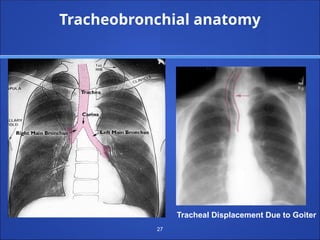

Tracheobronchial anatomy

Tracheal Displacement Due to Goiter